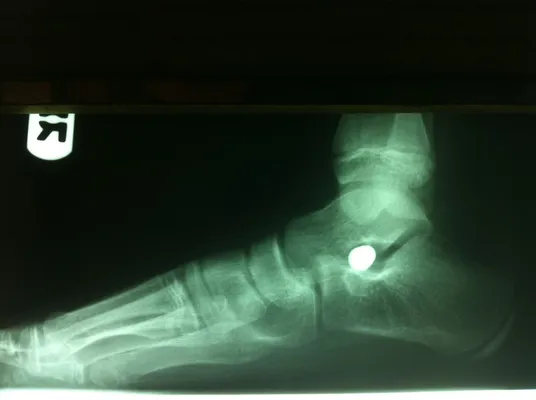

Pre-operative x-rays of the flatfoot with the talus deviated medially due to subluxing off the calcaneus causing the midtarsal joint to sublux laterally and uncovering of the talar head at the talo-navicular joint (left). The talus bone should line up with or be close to paralletl with a line drawn through the 1st metatarsal shaft (right). This is referred to as Meary's angle.

One case see an improvement in Meary's angle after surgical repair of the flatfoot with a subtalar joint implant which blocks the subluxation of the talus off of the calcaneus.